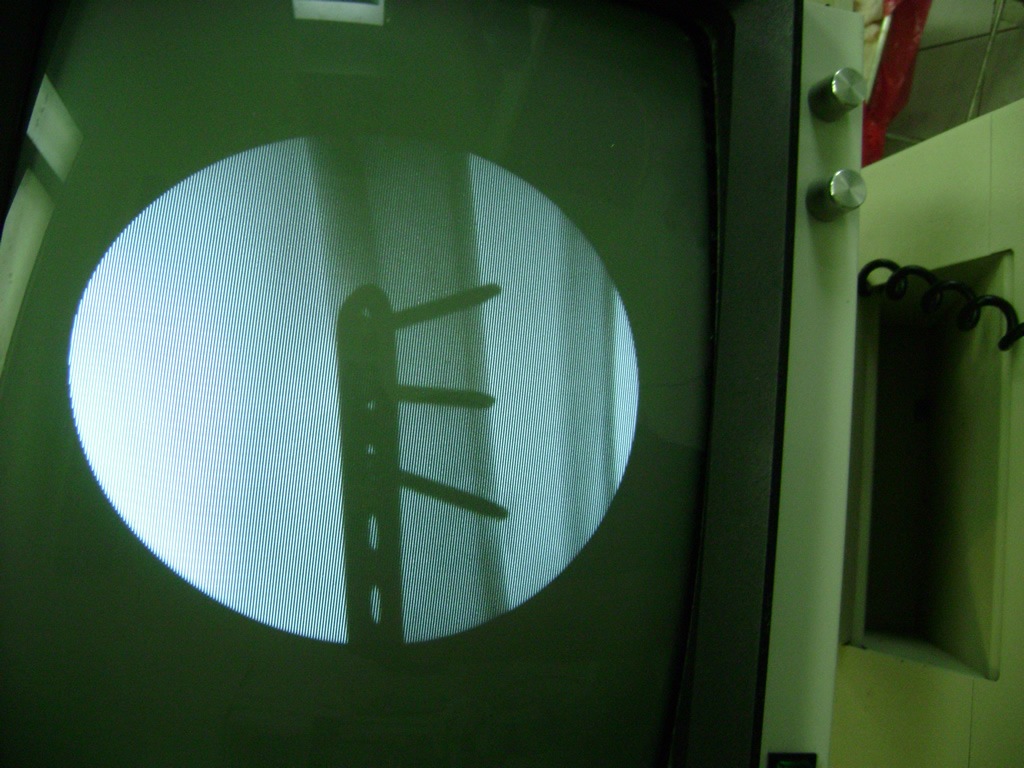

Aunque cada uno de estos huesos puede fracturarse por separado, normalmente la rotura es una lesión que se produce de forma conjunta

La mayor parte de las roturas implican a la parte proximal del hueso (parte del hueso próximo a la rodilla) o a la parte distal (parte del hueso cerca del tobillo).

Debido a la fina cobertura de piel que recubre la tibia y el peroné, las fracturas generalmente son abiertas, es decir, el hueso roto rasga la piel, atravesándola. Las fracturas de tibia y peroné generalmente se producen por un fuerte impacto o torsión.